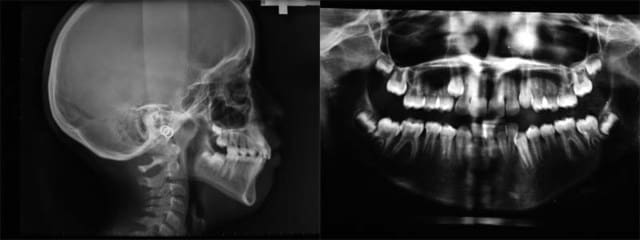

je vais préparer les photos, voici les Rx. éclaircies

Rx - Eugenol